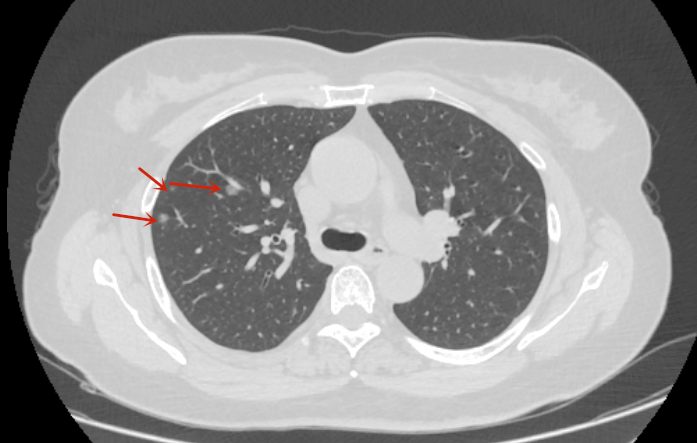

患者张女士在体检中发现右上肺多发结节结节,最大直径约1.2cm,经影像学评估后,医生建议行右上肺叶切除术。术后病理确诊为微小浸润性肺腺癌,属于早期肺癌。目前患者恢复良好,术后无需接受化疗,仅需定期复查。

▲胸部CT是右上肺、右中肺多发肺结节(箭头所示)